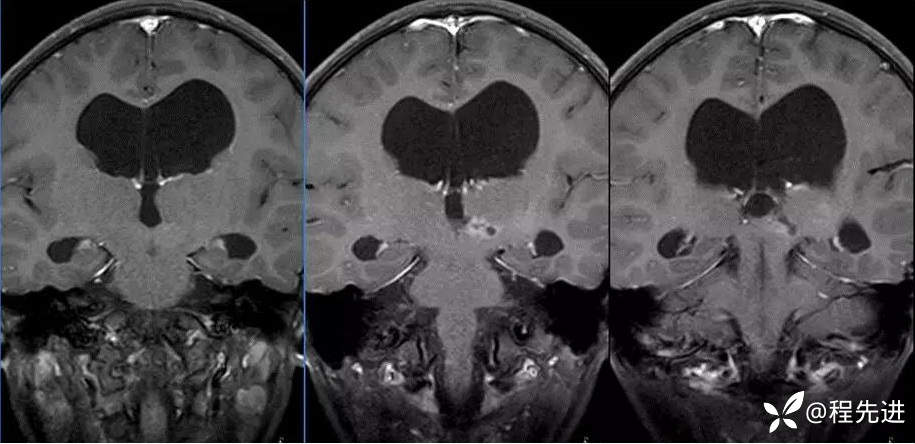

MR